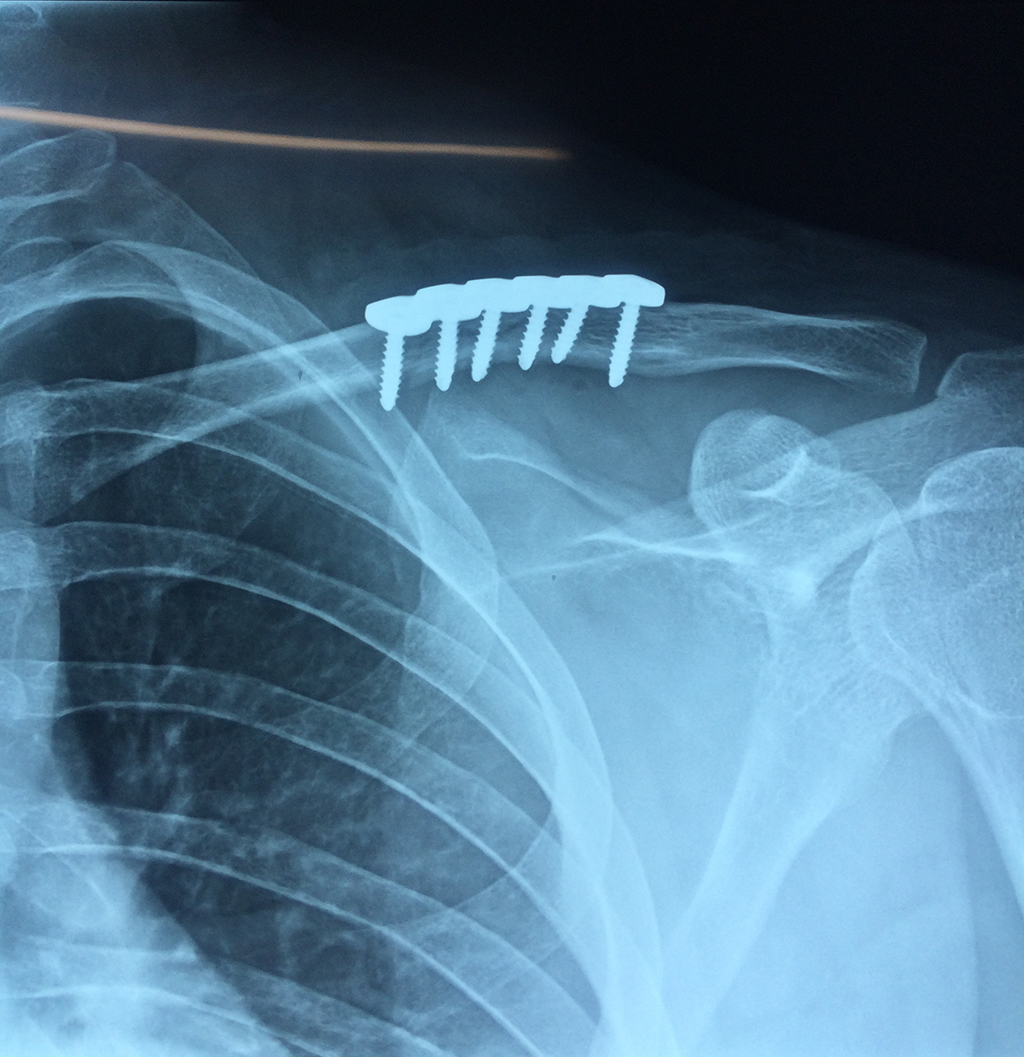

Clavícula

La clavícula es un hueso largo, con forma de "S" itálica, situado en la parte anterosuperior del tórax. Junto con la escápula forman la cintura escapular. Se puede palpar por toda su longitud y se extiende del esternón al acromion de la escápula, siguiendo una dirección oblicua lateral y posterior.

Se considera el único medio de unión entre el miembro superior y el tórax. A pesar de su aspecto, similar al de un hueso largo, posee una estructura semejante a la de un hueso plano, ya que carece de epífisis y de diáfisis, lo que la harían entrar dentro de la clasificación de hueso largo. Carece de un canal medular propiamente dicho.